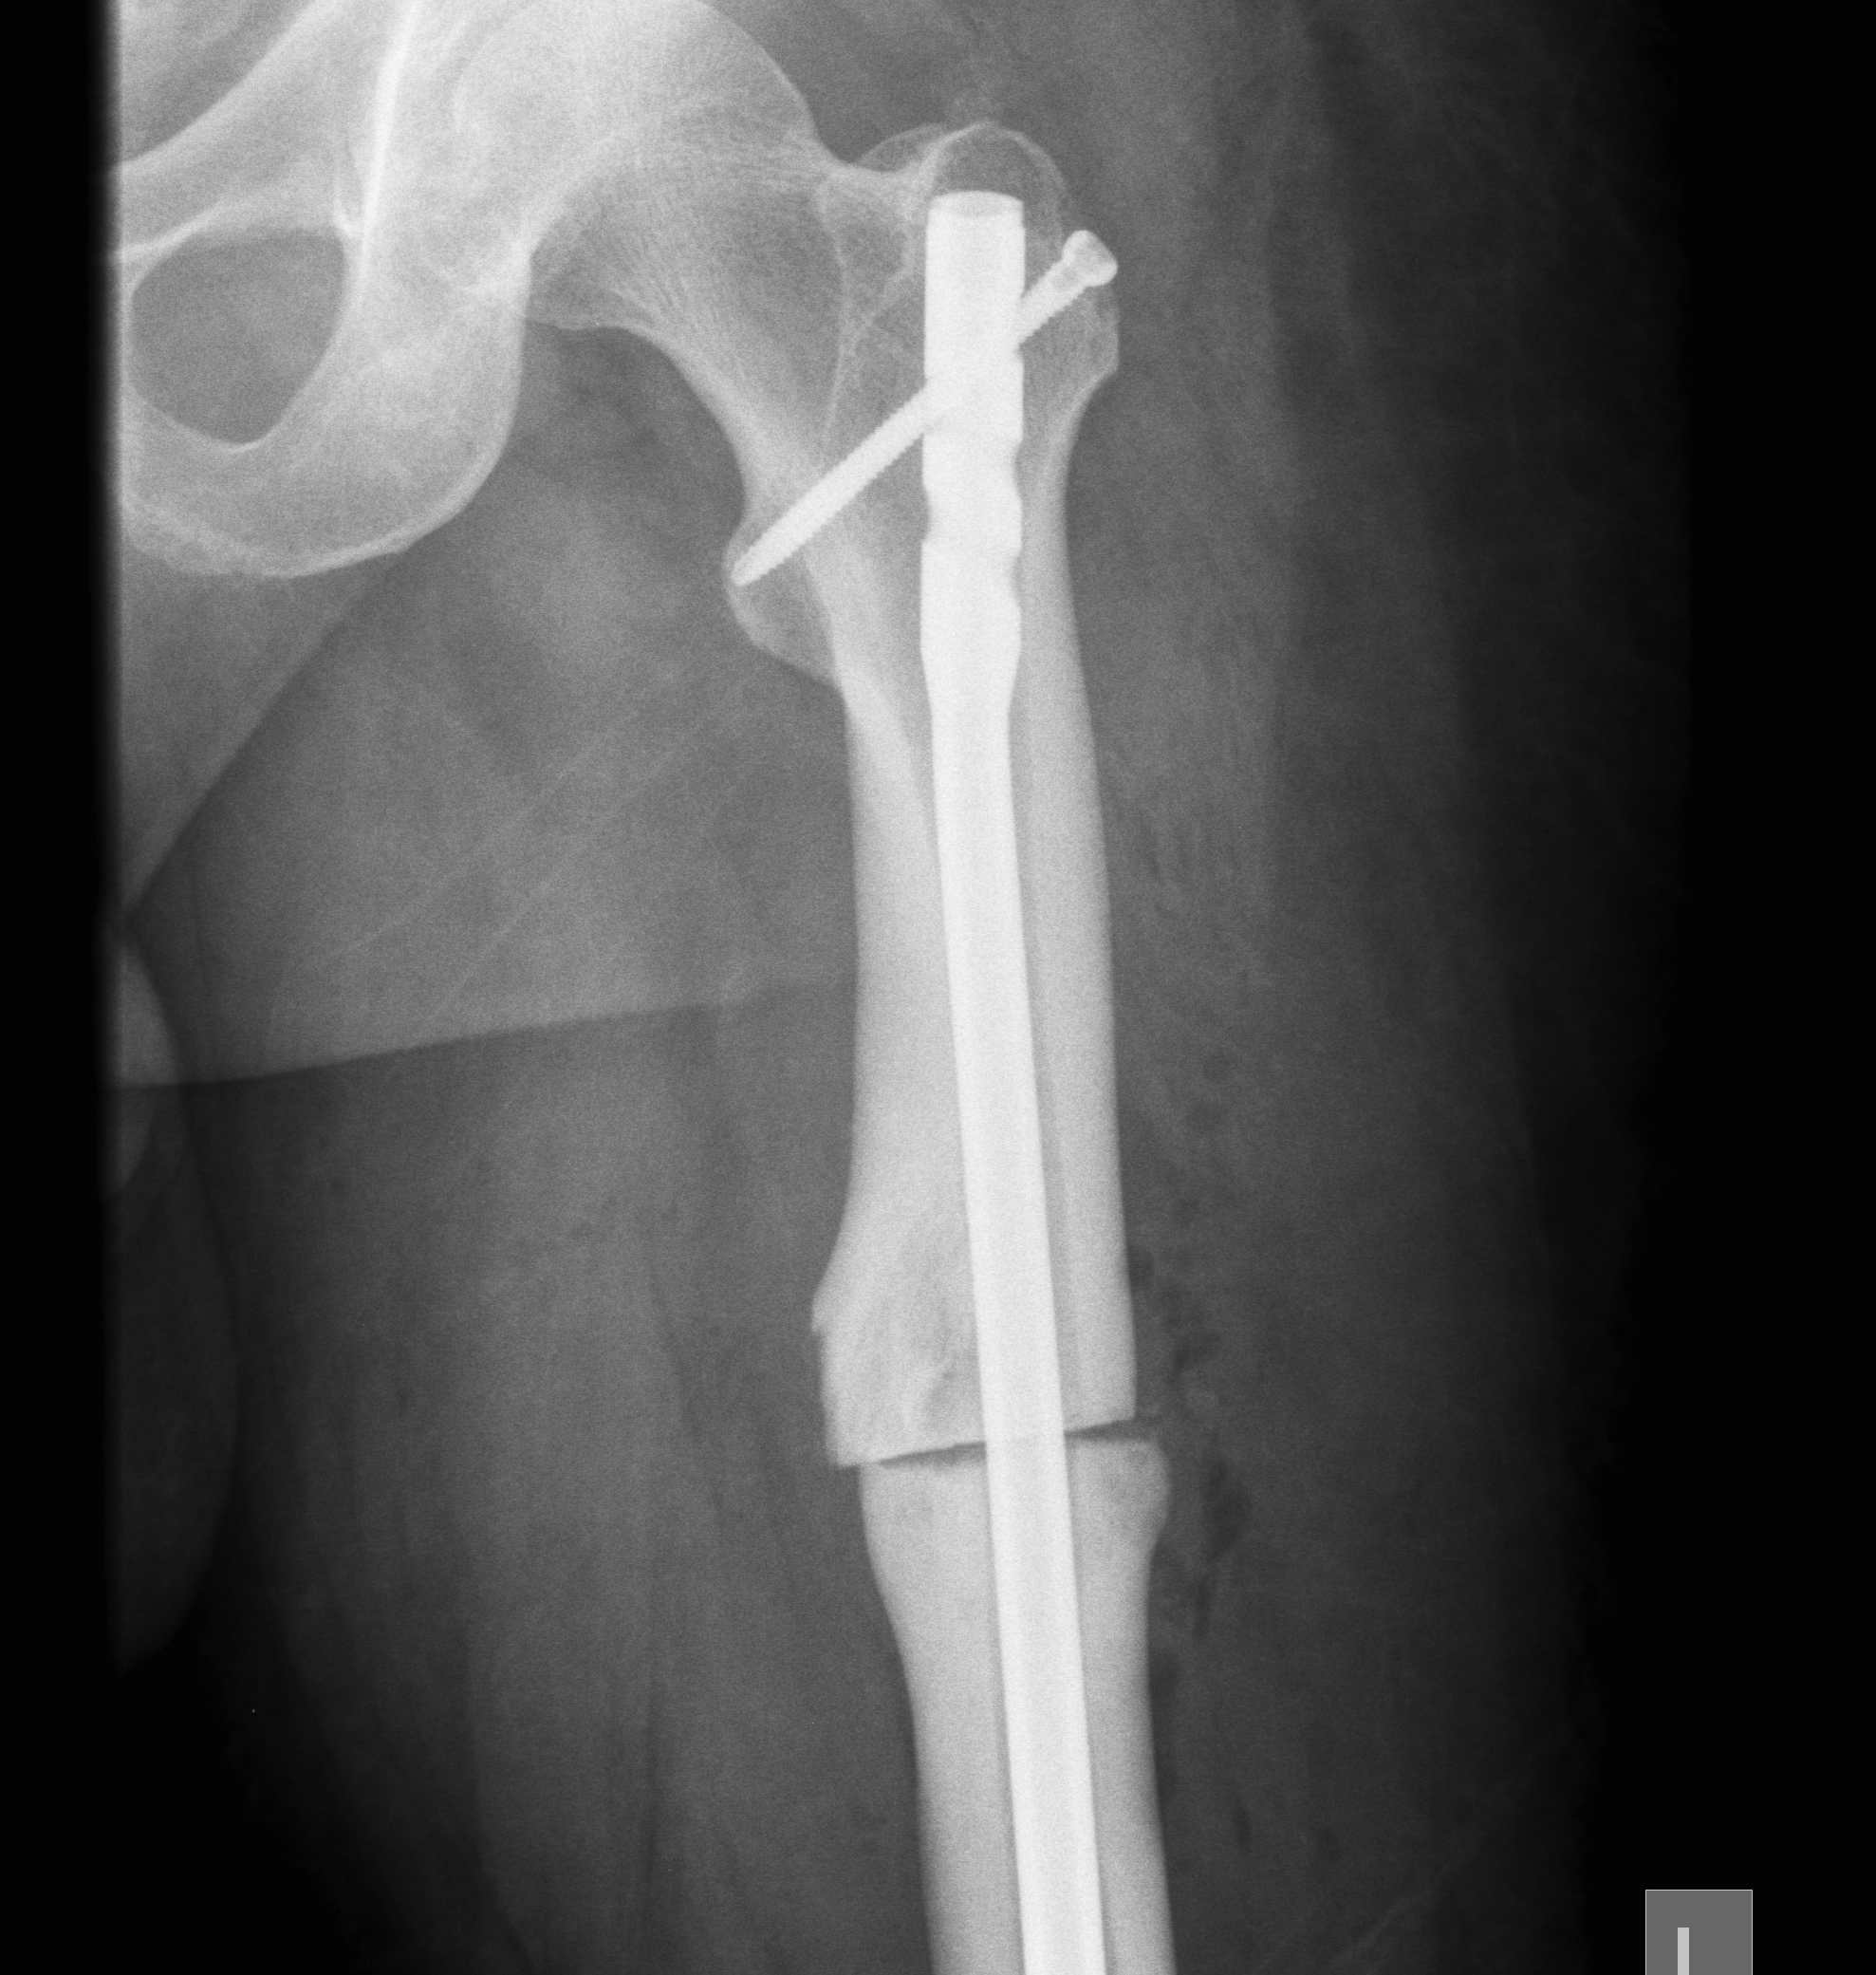

2. Osteotomy and TKR

Advantage

- bone preserving

- less bone resection to achieve correction

- augments not required

Disadvantage

- bigger procedure

- risk of nonunion

- must use stems to bypass

Technique

- medial opening wedge osteotomy

- preserves bone